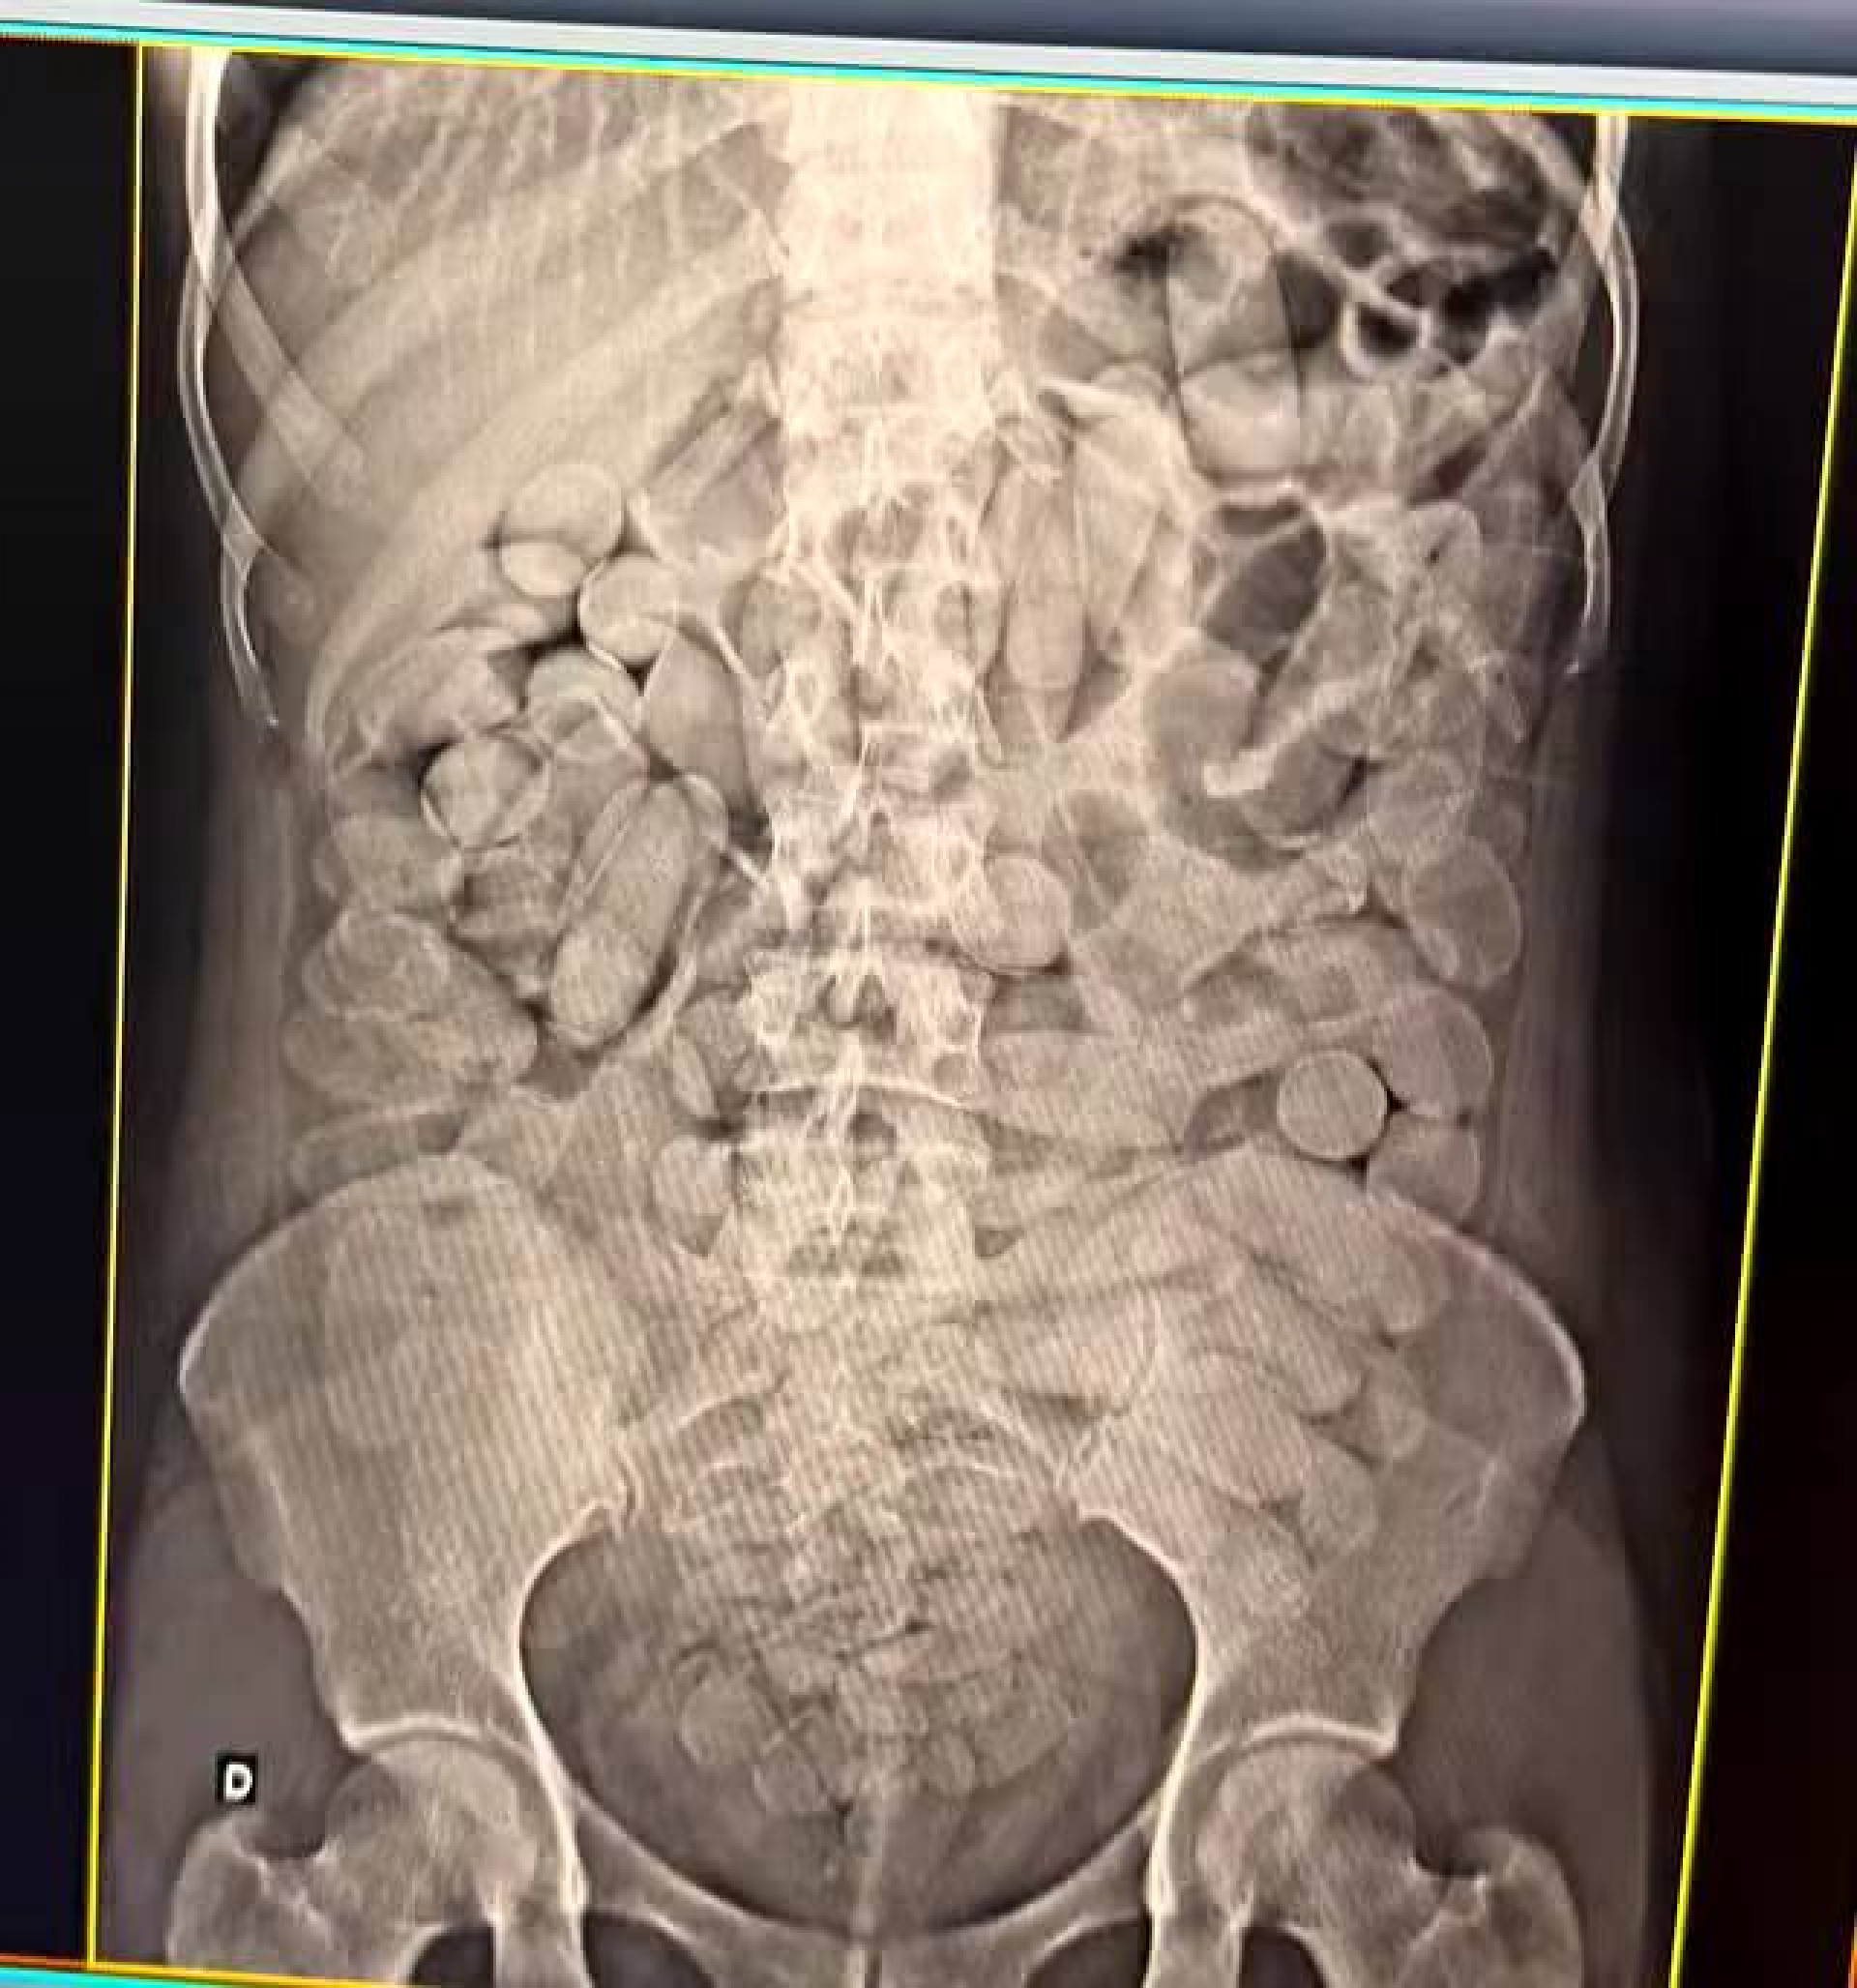

Mulheres engoliram diversas capsulas e foram encaminhadas ao hospital Divulgação/Receita Federal

As detidas seguiam em veículo clandestino quando foram abordadas. Após o flagrante, "as quatro mulheres  foram encaminhadas para o hospital, para expelir as cápsulas que haviam engolido".